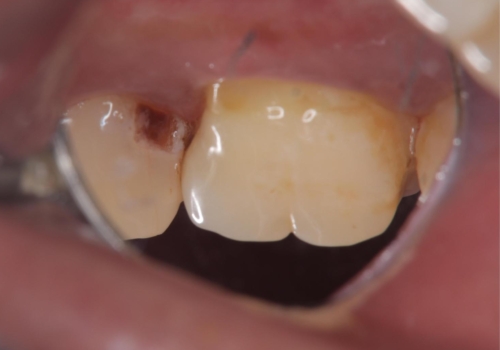

左上5番遠心に実質欠損を認め、さらに5番と6番の隣接面にもカリエスを認めました。6番の咬合面には、元々コンポジットレジン修復が施されており、劣化がみられたのでその部分も含め修復することとなりました。